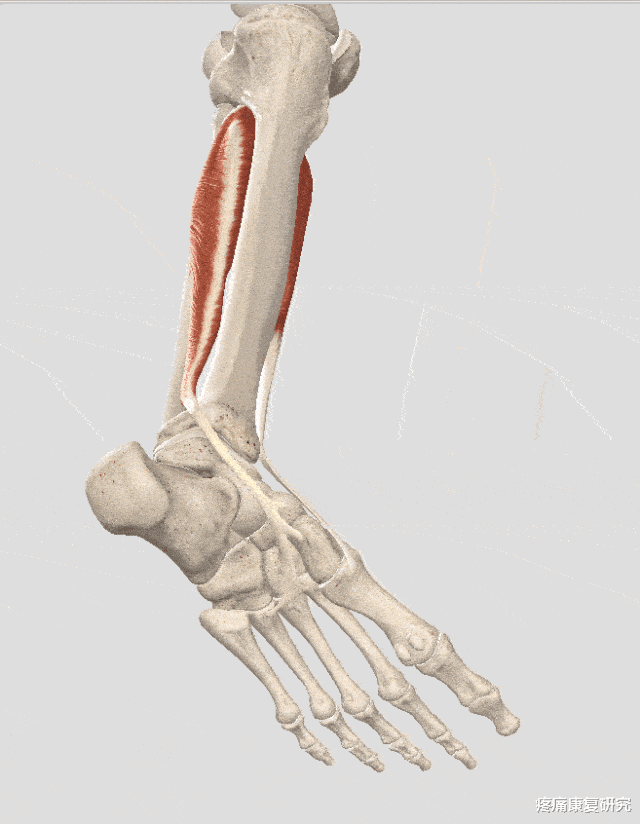

一、胫骨后肌的解剖与功能

1.解剖

起点:胫骨和腓骨后侧近端,骨间膜

止点:足舟骨粗隆及楔骨。

神经支配:胫神经(L4~S1)